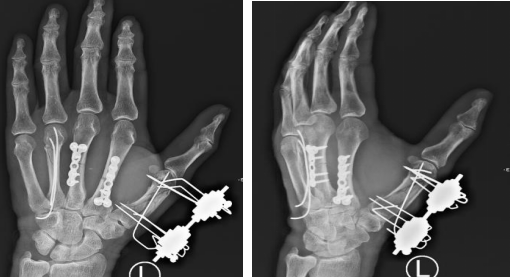

手外科一病区的滕道练副主任医师接诊,为患者安排查体,其左手背肿胀,几处开放性伤口,各长约1cm,创缘不齐,伤口深达掌骨,各指指端色红润,感觉良好,手背局部压痛,可触及骨擦感,各指可主动伸屈活动,幅度欠佳。左手正斜位X线片示:左手多发掌骨骨折,其中第1掌骨闭合性粉碎性骨折,第2、3掌骨横形骨折,第4掌骨头下骨折。

手术团队组织讨论手术方案,根据骨折类型不同,需采用不同的固定方式。第1掌骨为闭合性粉碎性骨折,采用闭合复位后,单纯支具外固定难以维持,单纯使用克氏针固定骨折端,骨折端不稳定,不利于早期康复锻炼。考虑使用IMEF(Ilizarov显微手足外固定器)固定,避免切开复位对骨折血供的影响,最大程度上避免了骨折不愈合。连接杆将克氏针固定为一整体,达到了微创并且稳定的治疗目的。第2、3掌骨为横行骨折,行切开复位接骨板内固定。第4掌骨头下骨折,骨折错位,需行内固定术,内固定选择髓内钉。

术后X线片